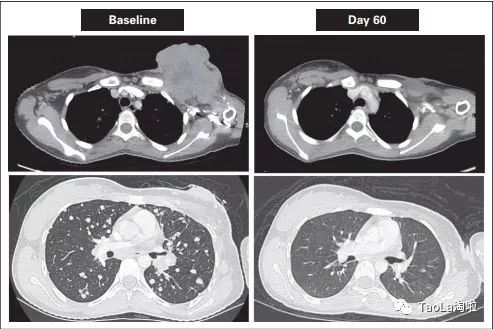

乳腺癌:

50岁女性

治疗前:这位患者之前接受过多次的化疗和手术治疗,无奈最后肿瘤还是复发了,情况很严重

治疗后:使用了抗癌药Vitrakvi治疗20天之后,裸露的肿瘤几乎消失了。